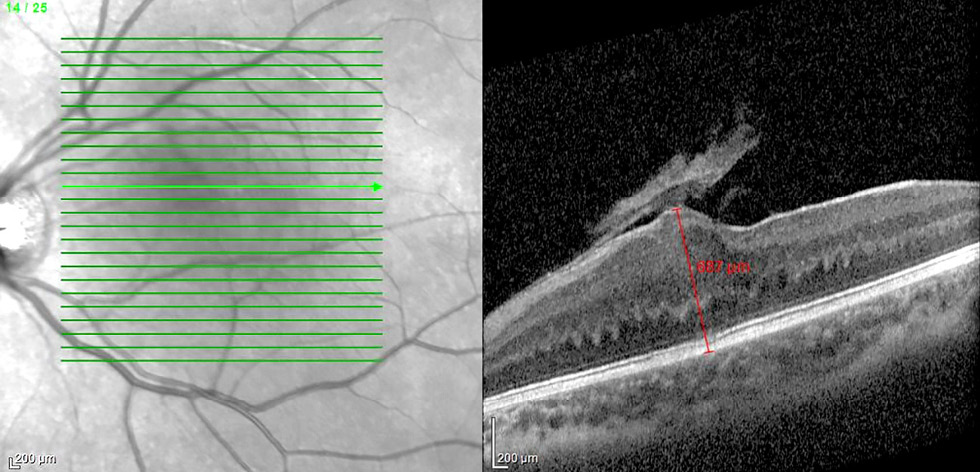

При офтальмоскопии определяли проминирующее образование сероватой окраски с нечёткими контурами, ЭРМ и аномальным ходом ретинальных сосудов над образованием и перифокально (рис. 1).

Рис. 1. Офтальмоскопическая картина комбинированной гамартомы сетчатки и ретинального пигментного эпителия макулярной локализации у ребёнка 1,4 года: проминирующее образование сероватой окраски с нечёткими контурами, эпиретинальной мембраной и аномальным ходом ретинальных сосудов.

Fig. 1. Ophthalmoscopic image of combined hamartoma of the retina and retinal pigment epithelium of macular localization in a 1.4-year-old child: a prominent grayish lesion with blurred borders, an epiretinal membrane and abnormal retinal vessel course.